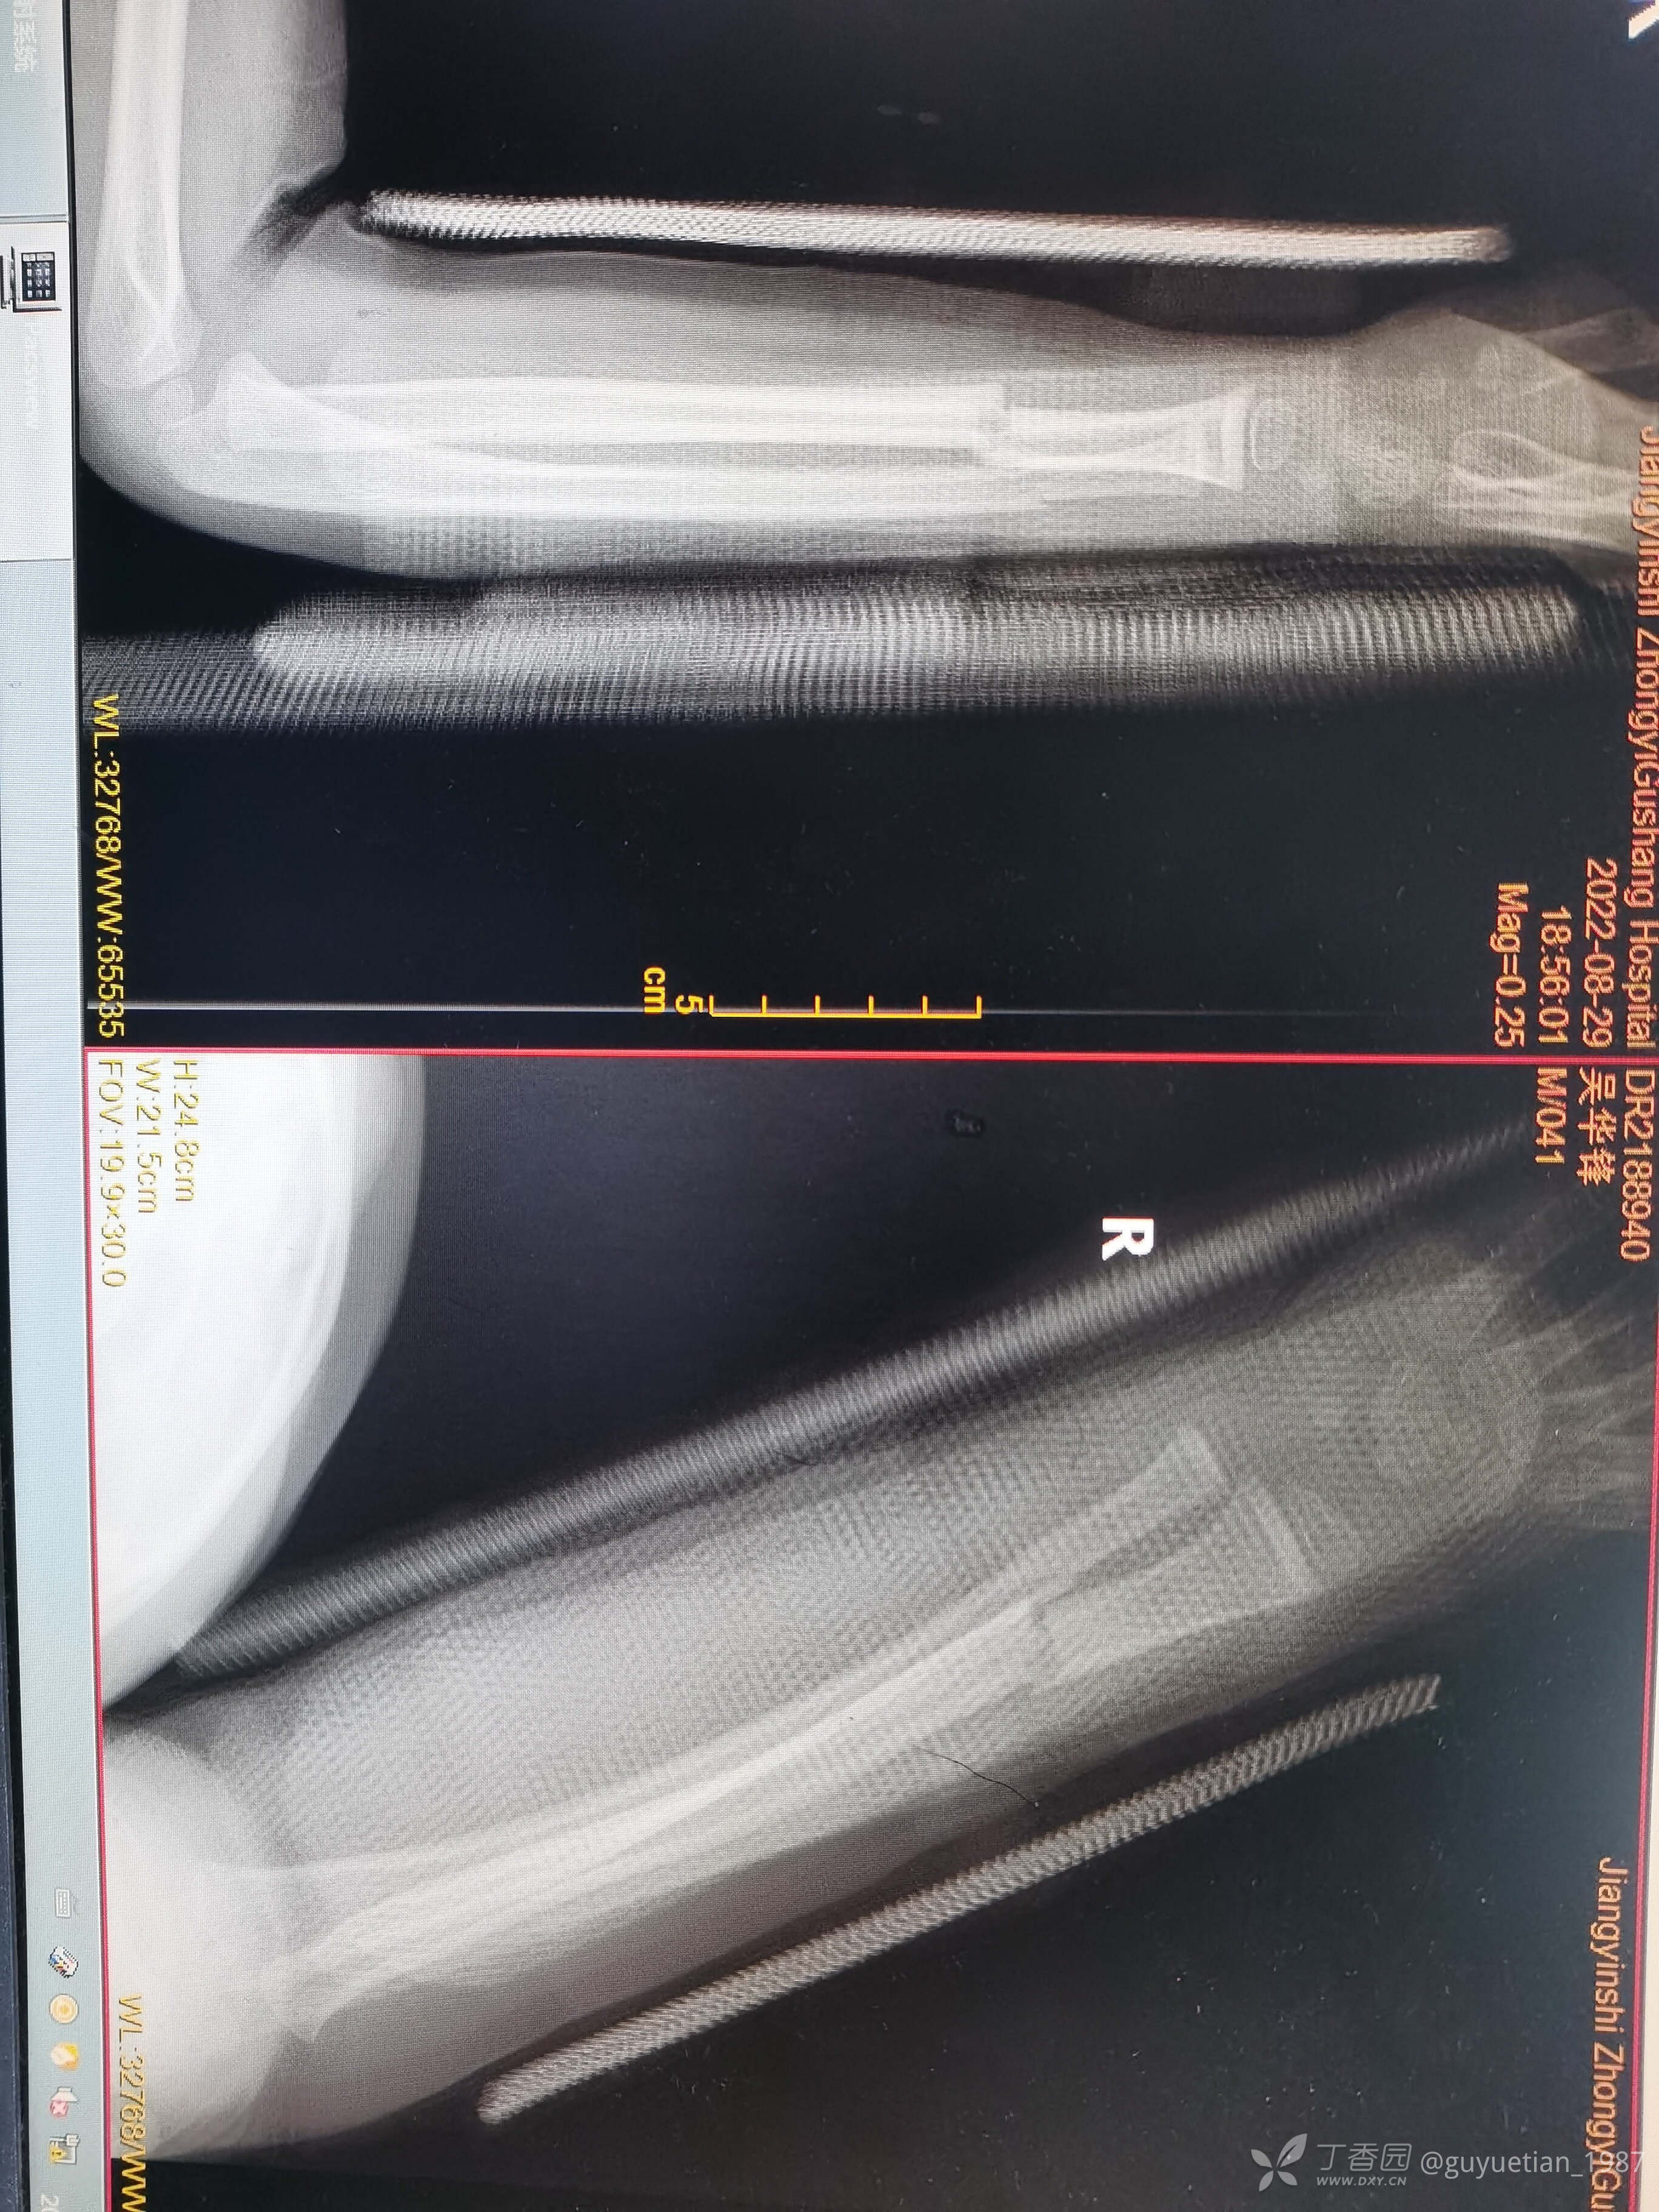

患儿6岁,夜急诊遇见他前两月余同一手臂桡骨青枝骨折,保守治疗后顺利愈合。

果然儿童前臂骨折很容易发生二次骨折。夜急诊来院,尺桡骨中远1/3双骨折。即刻复位,自制小夹板旋后位固定,复位并不理想,与家属沟通病情(手术与保守的利弊),家属充分理解后选择保守治疗。